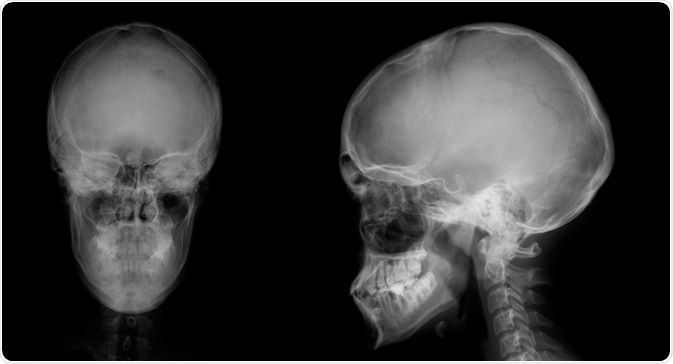

Multiple osteomas also occur in Gardner's. The most common site for these types of tumors is the mandible, specifically at the angle of the jaw and the inferior surface of this bone. Additional osteomas may be present in the skull, paranasal sinuses, and long bones.

Image Credit: vanzittoo / Shutterstock.com

Osteomas occur early in the course of the disease, typically before colonic polyps become symptomatic or are picked up by radiography. In fact, it is not uncommon for osteomas to develop in Gardner syndrome patients before the condition is even diagnosed. For this reason, the presence of osteomas should arouse curiosity as to the presence of Gardner’s syndrome, as they offer a window of opportunity for early diagnosis and possible prevention of colonic cancer. A number of researchers, therefore, suggest that radiography of the mandible may help to screen for carriers of this condition.

Both osteomas and odontomas may cause the face to become asymmetric. Both sharply-defined radio-opaque lesions as well as fuzzy radio-opaque lesions can be visualized in patients with Gardner's syndrome.